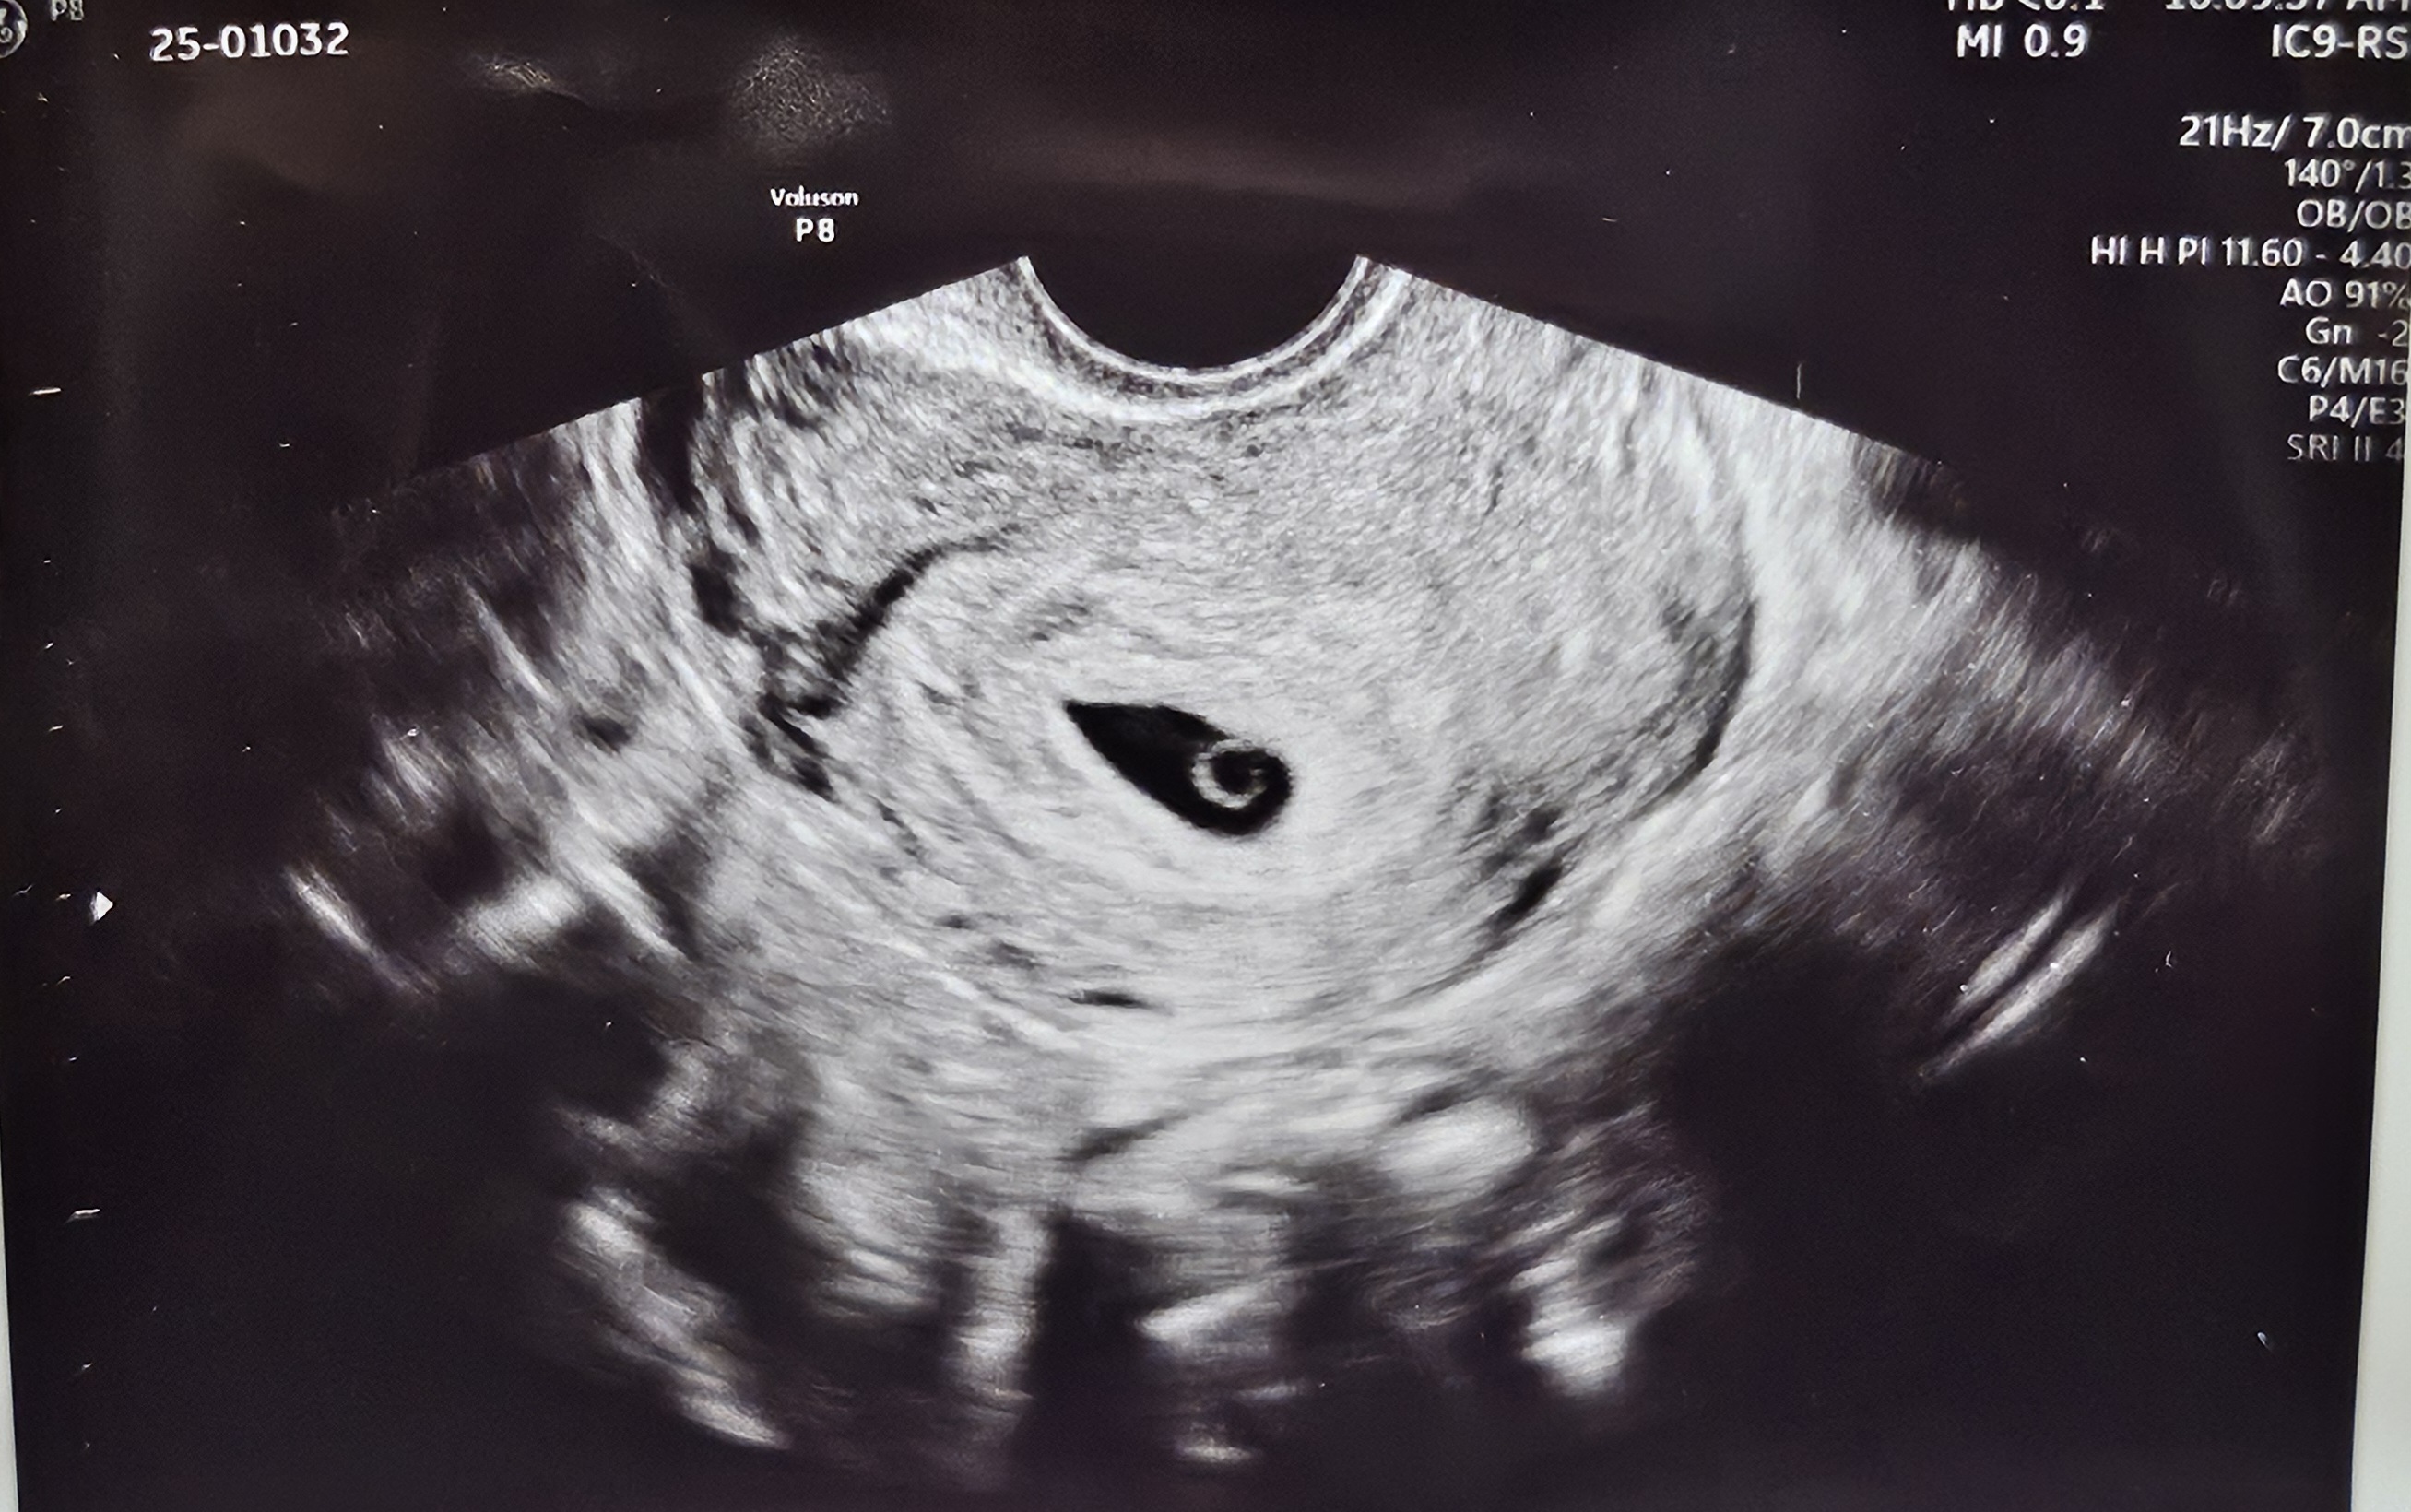

저건 너무 이쁜 난황이죠!

난황 맞나요

지난번에 유산하고 이번에 다시 임신한 초보산모입니다 지난번엔 난황을 보지 못했어요... 이번엔 난황 맞죠... 기뻐해도 될까요 ㅜ.ㅜ

너무 예쁜 난황인걸요!축하드려요!

실눈뜨고 봐도 난황이네요 ㅎㅎ 축하드려요

네! 이쁘게 난황 잘 자리잡아있네요☺️